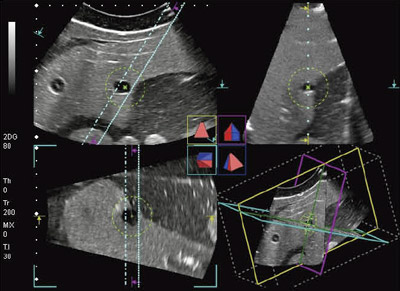

図3は,4D造影超音波モードのMPR(Multi Planer Reconstruction)表示の例である。図3 aに示すとおり,走査方向をA面,揺動方向をB面,体表に平行面をC面と定義する。図3 bは,ソナゾイド投与下の早期相であり,直交3断面の造影像と,右下に動脈血流のボリューム像が表示されている。

図4は,A面のMulti View表示による5mm間隔での腫瘍の造影像と,C面のMulti View表示である。三次元的に腫瘍の広がりを観察できるので,適切なマージンをもって腫瘍を焼灼可能なラジオ波焼灼療法(RFA)の針先位置を決定できる。また,治療前後の3D造影像を比較することにより,焼灼範囲の評価が可能である。

PVT-375MVに穿刺アダプタを装着して穿刺を行う際は,画面上に穿刺アダプタに対応した穿刺ラインが表示される。図7は,4D穿刺モードにおけるファントムのMPR表示である。A面に表示された斜めの2本のラインは,穿刺アダプタの穿刺経路に対応したガイドラインである。平行した2本のラインは,穿刺経路の左右5mmに位置している。MPRのB面は,穿刺経路を交線とする直交面である。A面のガイドラインの範囲内で穿刺針が刺入されたとき,B面中央の破線上を進むことになる。そして,C面は,穿刺経路に直交する。4D穿刺モードのMPR表示では,穿刺経路に対する直交3断面が表示されるので,穿刺針の刺入時に周囲組織との関係の把握が容易である。

さらに,図7に示されるように,任意の半径の球面(ターゲットガイド)を表示することが可能で,腫瘍の広がりやRFAの焼灼範囲の目安として利用することができる。図8に,4D穿刺モードにおけるMulti View表示のファントム像を示す。B面のMulti View像(図8 a)は,穿刺経路に平行な断面の並列表示であり,C面のMulti View像(図8 b)は,穿刺経路の深さごとの断面の並列表示である。腫瘍の広がり,周囲臓器や周囲血管の位置,焼灼範囲の評価が容易である。図9は,RFA治療中の4D穿刺モード像である。ガイドラインに沿ってRFA針が刺入され,焼灼されている。ターゲットガイドの球面を目安に,焼灼状況を三次元的に観察することができる。